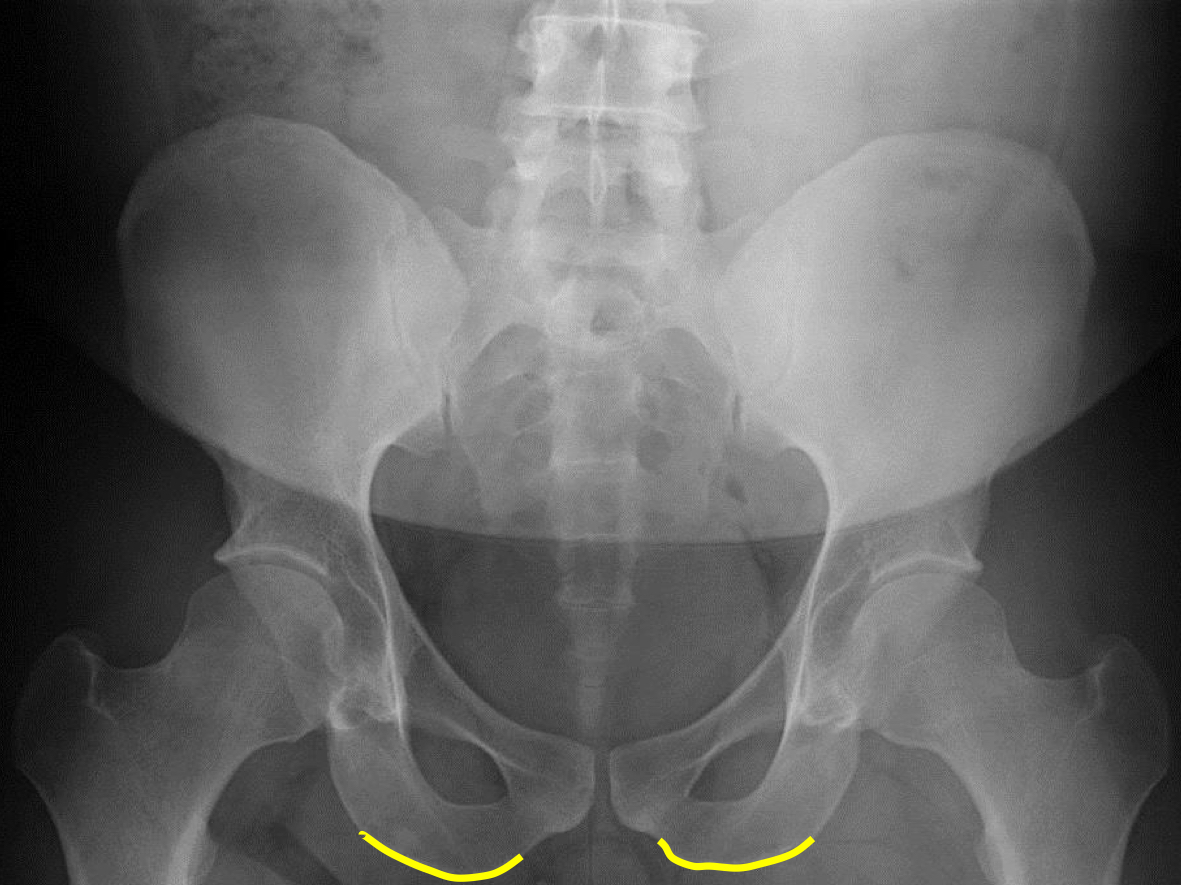

What view is this?

AP (Anterior to Posterior) LumboPelvic

What is this?

Femur Heads

What is this?

Superior Iliac Crests

What is this?

Lateral Iliac Crests

What is this?

Ischial Tuberosites

What is this?

Obturator Foramen

What is this?

S2 Tubercle

What is this?

Pubic Symphysis

What is this?

Sacral Groove

What is this?

Lateral aspect of sacrum

What is this?

Medial Aspect of Ilium